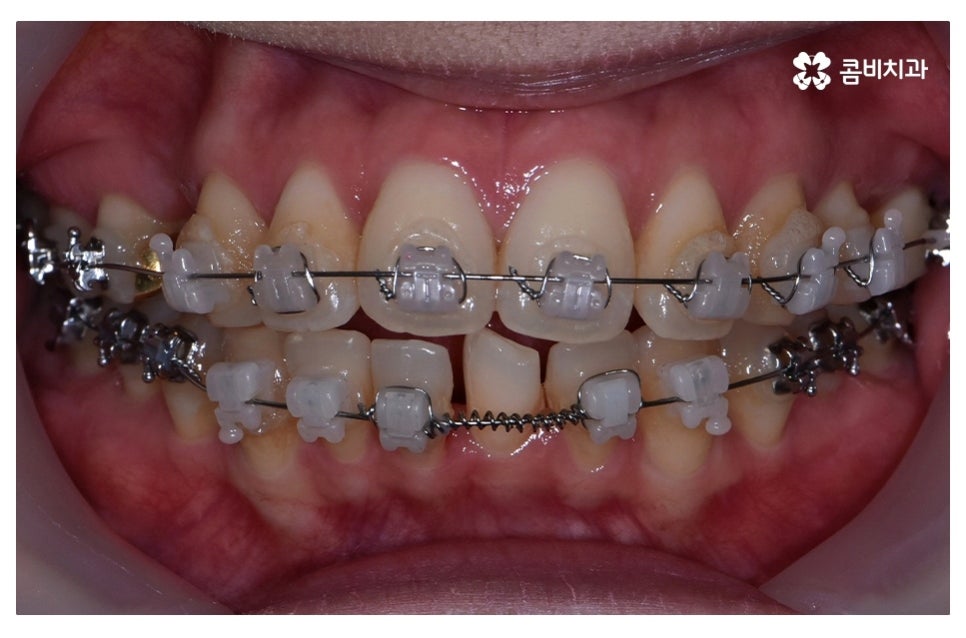

요즘은 교정 장치의 선택에 있어서 다양한 선택이 가능하지만

보편적으로는 본 포스팅의 사례처럼 클리피씨 교정이 많이 선호되고 있어요.

클리피씨 교정은 일반적인 교정보다 치료 기간을 단축시킬 수 있고

통증이 비교적 적으며 세라믹 재질로 심미적이라는 장점이 있어요.

위 환자분의 경우 덧니교정에 걸린 치료 기간은 약 24개월 정도이며

성인 이후에 치료를 진행한 사례라고 볼 수 있어요.